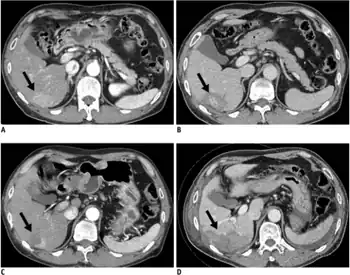

Triphasic contrast CT of hepatocellular carcinoma.

Ultrasound, CT scan, and MRI may be used to evaluate the liver for HCC. On CT and MRI, HCC can have three distinct patterns of growth:

A systematic review of CT diagnosis found that the sensitivity was 68% (95% CI 55–80%) and specificity was 93% (95% CI 89–96%) compared with pathologic examination of an explanted or resected liver as the reference standard. With triple-phase helical CT, the sensitivity was 90% or higher, but these data have not been confirmed with autopsy studies.[34]

a)Pre-ablation CT scan during arterial phase shows hepatocellular carcinoma nodule b) post-ablation CT scan during portal phase shows no definite residual enhancing tumor c) nine-month follow-up CT scan showing local tumor progression d) CT scan obtained immediately after second radiofrequency ablation showing complete ablation of recurrent hepatocellular carcinoma